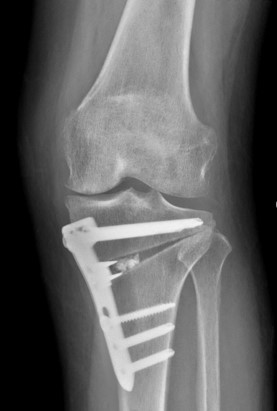

999.jpg 무릎 절골술 엑스레이 사진

무릎 관절염 치료는 크게 두 가지 방법으로 나뉜다. 첫 번째는 '인공관절 치환술', 두 번째는 '무릎절골술(HTO, DFO)'이다. 건강보험심사평가원의 데이터에 따르면, 무릎 관절염 수술 10건 중 약 7-8건이 인공관절 치환술이며, 무릎절골술은 2-3건 정도로 시행되고 있다.

인공관절 치환술은 미국에서 시작되어 1980년대부터 약 40년의 역사를 가지고 있는 반면, 무릎절골술은 1950년데부터 긴역사를 가지고 있으나 금속판의 문제와 절골술의 어려움으로 지체되다가 약 25년전부터 금속판의 문제를 해결하였고 약 15년전부터 무릎절골술의 수술기법이 발전되어 향후 지속적인 연구가 필요한 분야다.

무릎절골술은 자신의 관절을 유지하면서 체중 이동을 통해 통증을 완화하는 치료법이다. 이를 쉽게 설명하면, 치아가 완전히 손상되었을 때 임플란트를 하는 것이 '인공관절 치환술'이라면, 부분적으로 손상된 치아를 때우는 것이 '절골술'에 해당한다고 볼 수 있다.

즉 절골술은 자기관절을 이용하여 체중이동을 통해 통증을 줄이는 수술법이다. 인공관절술은 나쁜뼈를 없애고 특수한 금속과 플라스틱으로 교체하는 수술법이다

두 수술모두 좋은 수술법이나 수술의 적응증이 다르다. 즉 무릎관절염이 중기이고(KL 3) 나이가 70세 이하이면서 스포츠, 운동, 농사등의 활발한 활동을 한다면 절골술이 좋은 적응증이다.